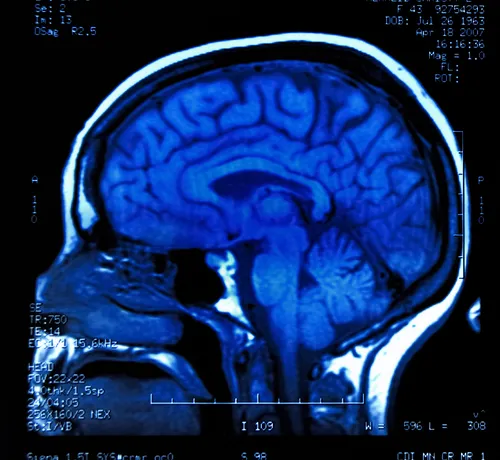

Magnetic resonance image (MRI) of the brainPhenytoin (generic form of Dilantin) is one of the first line antiepileptic drugs prescribed for many epilepsy syndromes.

Using magnetic imaging resonance imaging scans, the researchers examined the extent of cerebellar atrophy, finding that patients who were exposed to Dilantin long-term had more pronounced focal cerebral atrophy than patients in the control group.